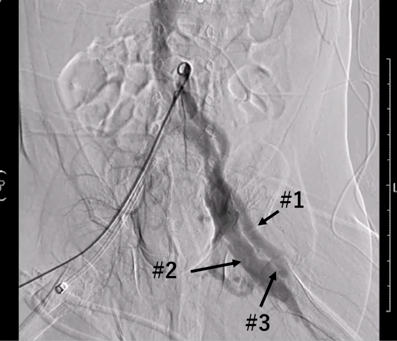

Lower extremity angiography was performed, which revealed a shunt from the left femoral artery to the left femoral vein. The SaO2 of the superior vena cava (SVC) was 62.6%, while the IVC was high at 94.1% (Fig. 2). We diagnosed a left femoral arteriovenous fistula and high cardiac output heart failure and performed arteriovenous fistula ligation on 78 days of life.

Journal of Pediatric Cardiology and Cardiac Surgery 5(2): 109-112 (2021)

Fig. 2 Lower extremity angiography

Shunt flow from the femoral artery directly into the femoral vein and the femoral vein dilation can be seen. #1: Left femoral artery, #2: Left femoral vein, #3: Arteriovenous fistula.